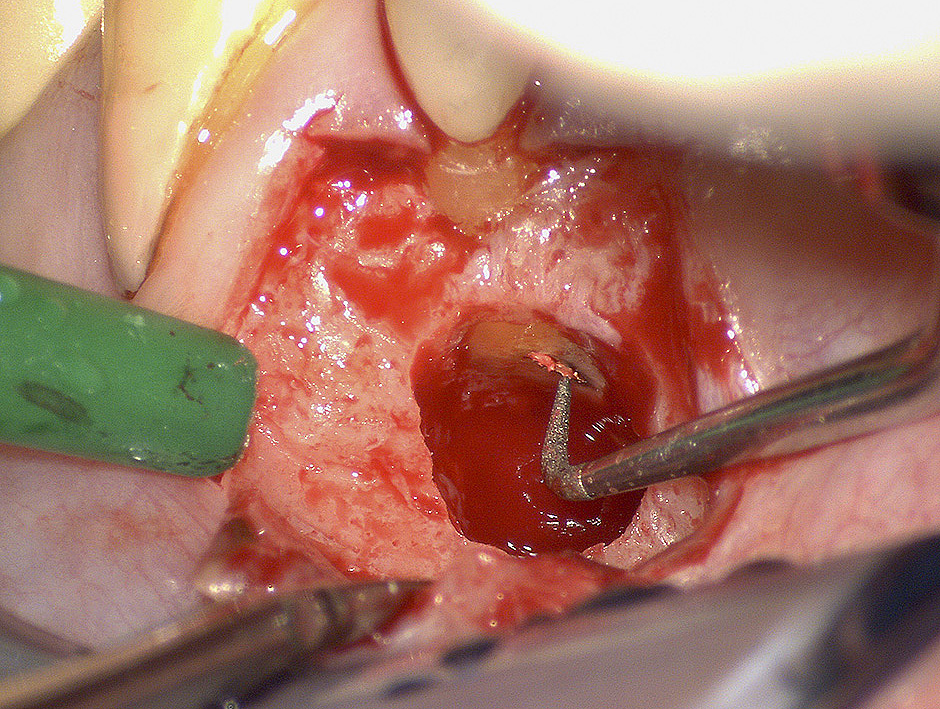

In chirurgia endodontica (apicectomie) il microscopio operatorio permette di individuare, osservare e curare ciò che ad occhio nudo o con ingrandimenti minori sarebbe impossibile vedere, mettendo in evidenza ogni piccolo particolare in modo chiaro ed evidente e di conseguenza alzando notevolmente il livello di cure e quindi di probabilità di successo al termine delle nostre terapie.